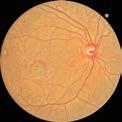

Using cultured human corneal endothelial cells for transplants could alleviate long waiting lists.

But just because something is obvious doesn’t mean it cannot be changed. For example, corneal donor shortages are a perennial issue, but human corneal endothelial cell (HCEC) transplantation could be a way to alleviate them, according to Dr Shigeru Kinoshita.

In his presentation titled “Primary Cultured Cells for Cultured HCEC Transplantation,” Dr Kinoshita said HCEC transplantation therapy using young donor allogenic cells could mean that “conceptually, one pair of donor corneas could be used for 300 patients in a safe and speedy procedure.” The challenge is proving the efficacy of using cultured human cells in the process.

Dr Kinoshita reported that the drive to prove the efficacy of cultured HCEC transplantation began in 2013, and during the intervening years he has published several papers on the topic. In that time, he has found that “cultured cells do not show chromosomal abnormalities, and around 85% survive 10 years after transplantation.”

In a subsequent clinical trial, Dr Kinoshita divided patients into two groups: one with mature differentiated sub-population cells of less than 76.3%, and another with most cells reaching maturation of 94.6%. The results showed that group 2 exhibited significantly higher endothelial density compared with group 1, and cell shape was significantly improved even after three years post-op.

These results highlight the presence of rejuvenation, according to Dr Kinoshita. He added that the Japanese government has since approved Vyznova as a treatment for corneal endothelial failure, and that 180 HCEC transplants involving the use of this medication will take place in the country this year, up from just 25 in 2024.

HCEC transplantation is also frequently used by Dr Kinoshita’s university for a wide range of conditions. Bullous keratopathy is the most common condition, followed by glaucoma drainage bleb, failed graft, and Fuchs’ endothelial dystrophy.

Dr Kinoshita is now aiming at making cultured HCEC transplantation a “global standard medicine,” with phase 2 and 3 trials currently underway in Japan. Culture cells have been shipped to El Salvador, where 90 cases are currently underway as part of a phase 1 clinical trial. Meanwhile, phase 2 trials are ongoing in the United States and Canada.